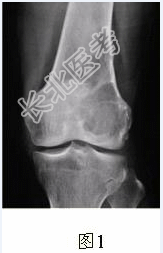

- [材料题] 患者女,35岁,左膝关节隐痛1年余,近1周加重,活动后明显疼痛。查体:左股骨下端外侧肿胀,压痛。行左膝关节正侧位CR,并行左膝关节CT扫描,见下图。

- 简答题1、根据膝关节CR和CT影像,你认为此病例的影像学表现有?

- 简答题2、对本病例,应首先考虑的诊断是?